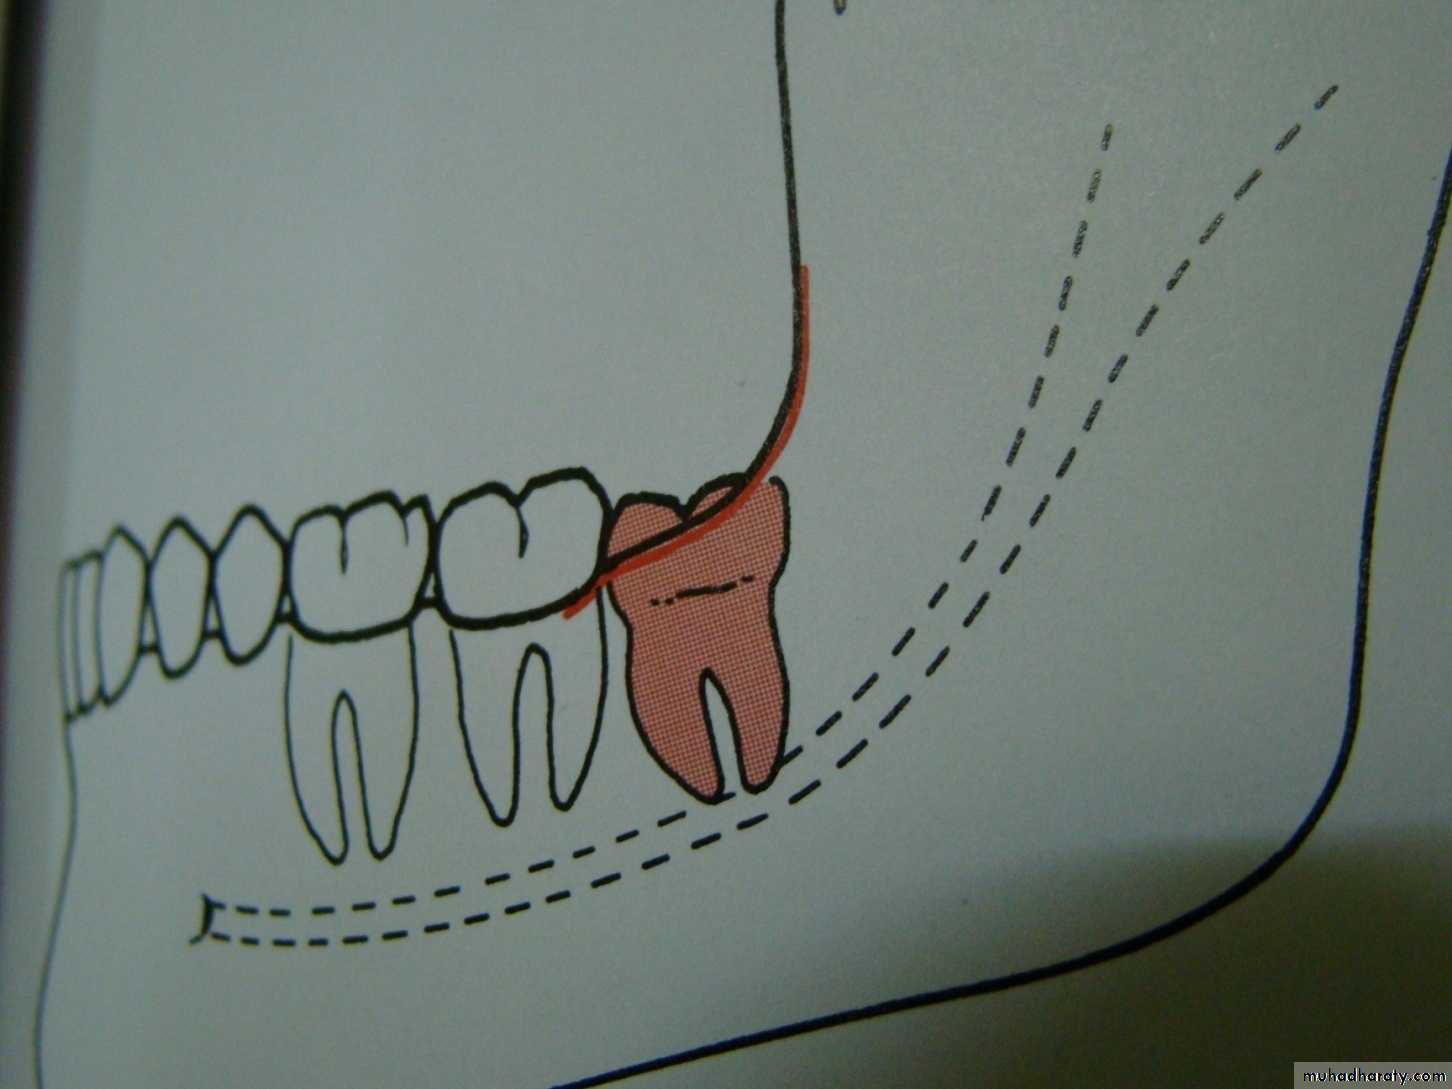

Winters classification of impacted lower third molar

Mesio angularDisto angular

Horizontal

Vertical

Inverted

Transverse

Buccoversion

Linguversion